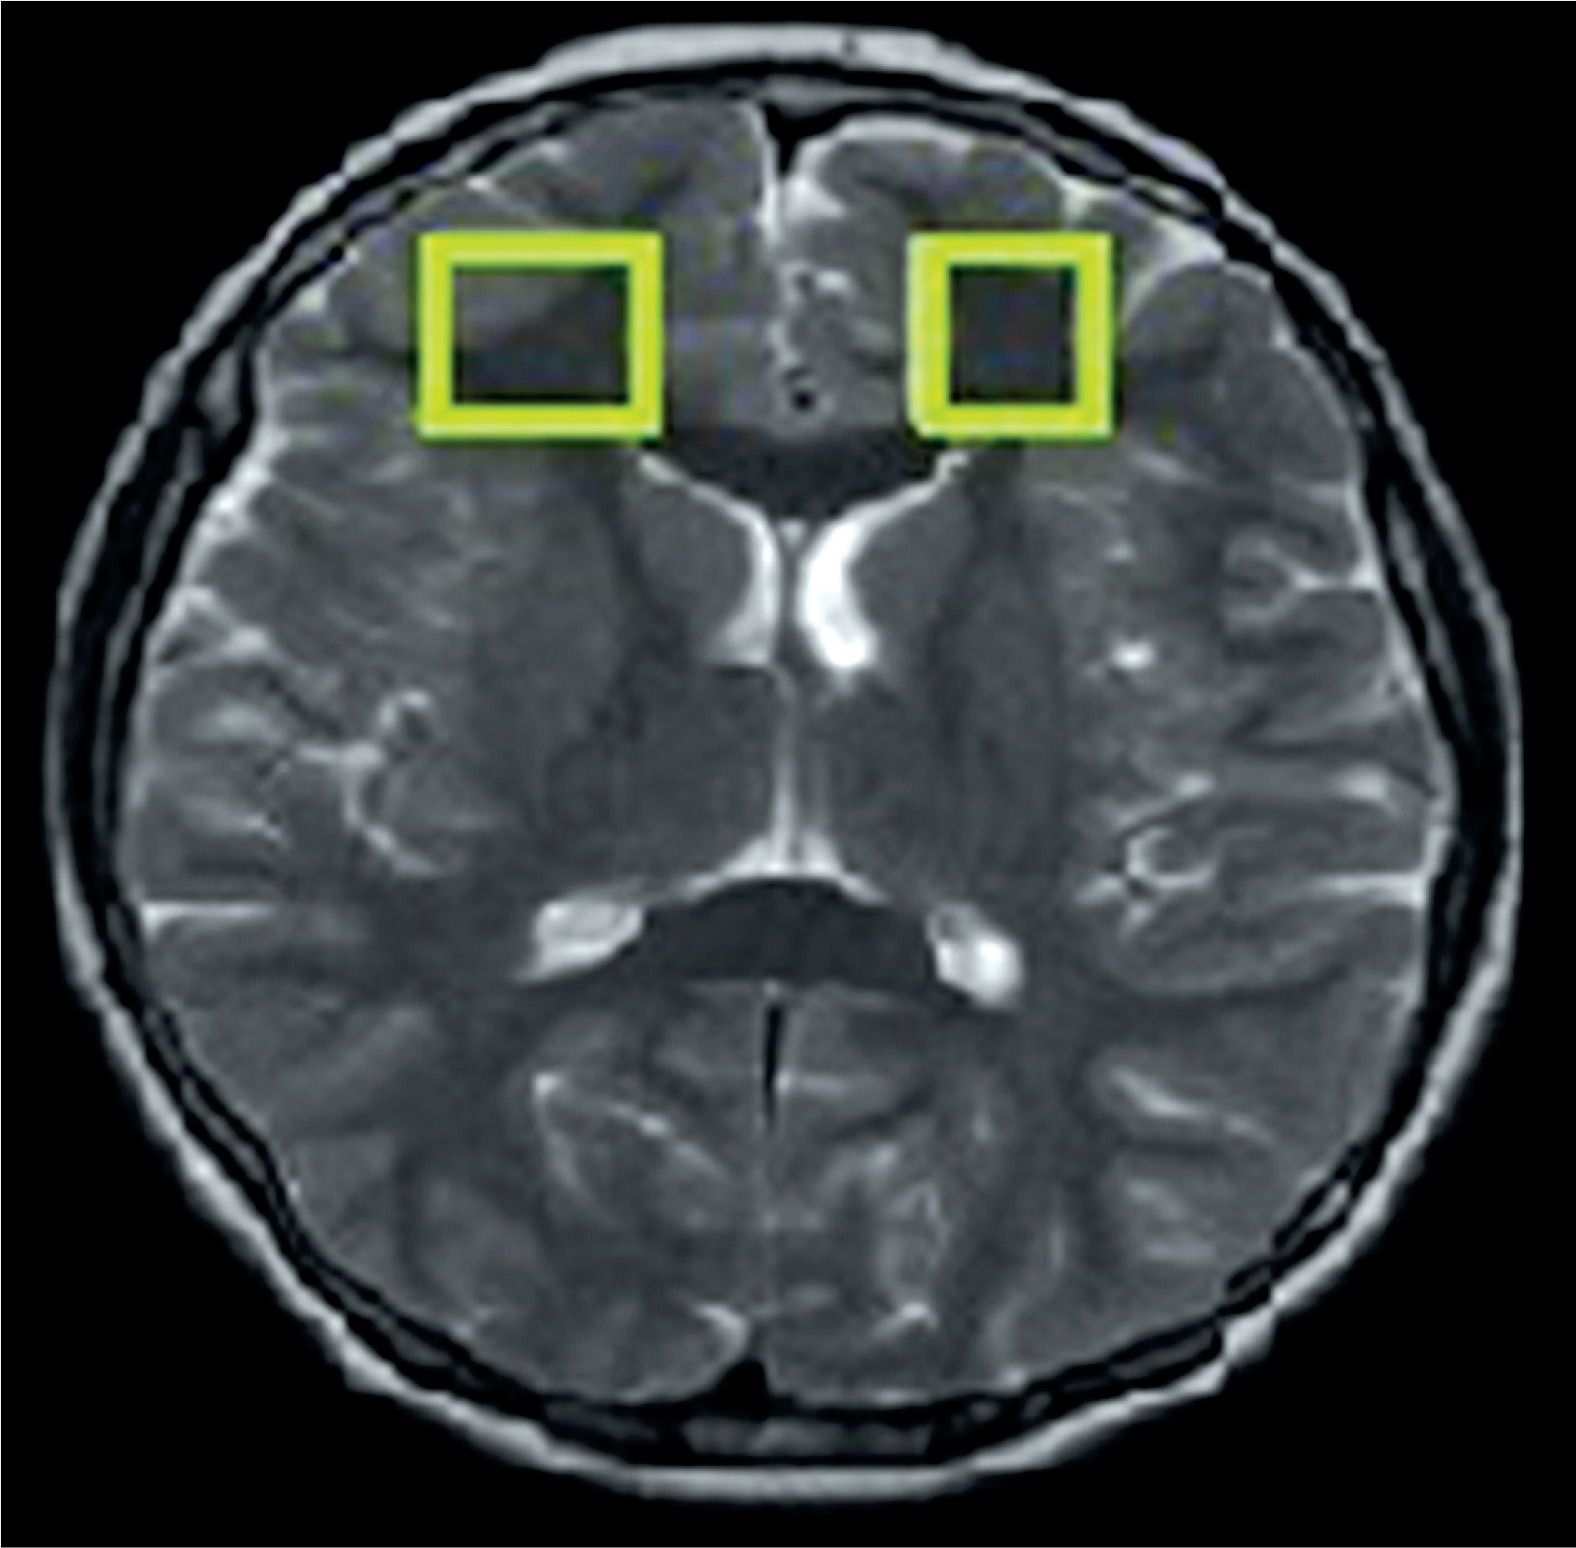

The examinations were performed with MR Signa HDxt 1.5 T (GE) using a transceiver head coil. The 1H-MRS was carried out using the Point-Resolved Spectroscopy Sequence (PRESS) method (TE = 35 ms, TR = 1500 ms, number of acquisitions = 128, slice thickness = 20 mm). Spectroscopic signal was acquired from volumes of interest (VOIs 2 × 2 × 2 cm) in the left and right frontal lobes (Figure 1). A quantitative analysis of the spectroscopic data was performed using SAGE 7.0 dedicated software (Spectroscopy Analysis, GE). Concentrations of the specific metabolites (N-acetylaspartate – NAA, choline – Cho, myo-inositol – mI, lipids – Lip, lactates – Lac) were determined in relation to the concentration of creatine (Cr). Moreover, the mean concentration values were calculated for each hemisphere, then the concentrations in both hemispheres were added, and the total was divided by 2.

Figure 1

Volume of interest localised in the frontal lobe symmetrically in the right and left hemispheres